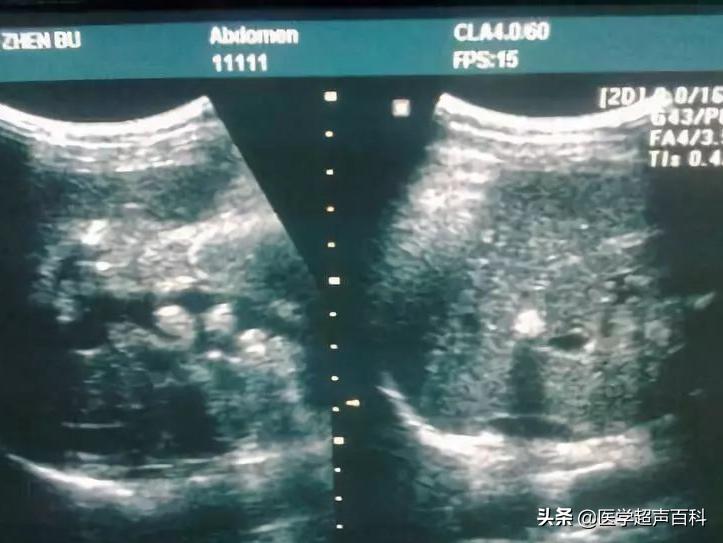

肝内钙化灶是指在超声或CT图像上肝脏内出现的类似于结石一样的强回声光团。右肝多于左肝,以20-50岁年龄段多见。人体肝脏有钙化灶的情况较多,可能与先天发育、钙磷代谢紊乱等因素有关;也可能因慢性炎症、肝脏外伤、脓肿等肝病痊愈后继发而成。单纯的钙化灶无明显症状,一般不会引起疼痛,对身体没有明显伤害,也无需治疗。

部分医院的超声医师容易把B超下的“强回声光团”状的肝内钙化灶误认为肝内胆管结石,使求医者误以为自己患有肝内胆管结石,有的因此乱用溶石及排石药,无形中增加了病人的负担。

所以B超发现肝内有“光团”后,要区别是肝内钙化灶还是肝内胆管结石,一个重要依据就是看远端胆管有没有扩张,而扩张的胆管内最容易形成淤滞性泥沙样结石。